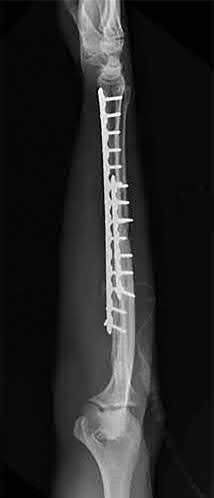

Question 12

A 55-year-old patient presents with a slowly enlarging, painful mass in the proximal humerus.

Biopsy reveals a hyaline cartilage matrix with cellular atypia, confirming a diagnosis of central conventional chondrosarcoma. Which of the following genetic mutations is most frequently identified in this specific tumor?

Explanation

Mutations in the isocitrate dehydrogenase genes, IDH1 and IDH2, are found in up to 50-60% of central conventional chondrosarcomas and enchondromas. EXT1 and EXT2 mutations are characteristic of multiple hereditary exostoses (osteochondromas). GNAS mutations are seen in fibrous dysplasia. TP53 and RB1 mutations are hallmark aberrations in osteosarcoma.